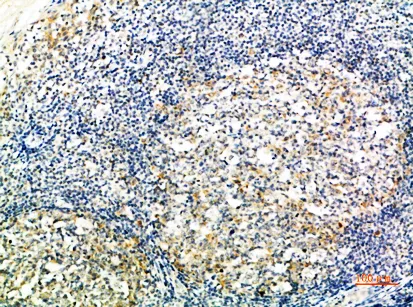

CD24 Rabbit Polyclonal Antibody($99/20μL)

Cat: APRab08302

Size1:20μL Price1:$99

Size2:50μL Price1:$118

Size3:100μL Price2:$220

Size4:200μL Price3:$380

Application:IHC-P,IF-P,IF-F,ICC/IF,ELISA

Reactivity:Human,Rat,Mouse

Conjugate:Unconjugated

Optional conjugates: Biotin, FITC (free of charge). See other 26 conjugates.

Gene Name:CD24 CD24A